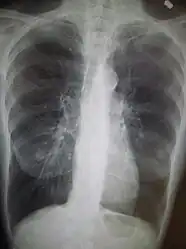

A chest X-ray and complete blood count may be useful to exclude other conditions at the time of diagnosis.[82] Characteristic signs on X-ray are hyperinflated lungs, a flattened diaphragm, increased retrosternal airspace, and bullae, while it can help exclude other lung diseases, such as pneumonia, pulmonary edema, or a pneumothorax.[83] A high-resolution CT scan of the chest may show the distribution of emphysema throughout the lungs and can also be useful to exclude other lung diseases.[25] Unless surgery is planned, however, this rarely affects management.[25] A saber-sheath trachea deformity may also be present.[84] An analysis of arterial blood is used to determine the need for oxygen; this is recommended in those with an FEV1 less than 35% predicted, those with a peripheral oxygen saturation less than 92%, and those with symptoms of congestive heart failure.[24] In areas of the world where alpha-1 antitrypsin deficiency is common, people with COPD (particularly those below the age of 45 and with emphysema affecting the lower parts of the lungs) should be considered for testing.[24]

- Chest X-ray demonstrating severe COPD: Note the small heart size in comparison to the lungs.